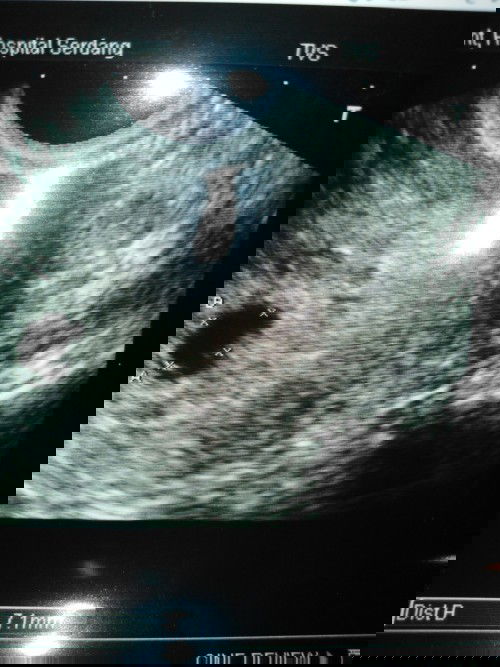

#miscarriage #Mommydaddyandyourbrothermissyou This picture is the last scan that shows you were in the heaven.. Mommy, daddy and your brother will gonna miss you... You always forever in our heart..

After work went back home take bath found out I'm bleeding in my whole panty. Then rushed to hospital for checking.. Doctor said I'm not active bleeding and I need more rest at home for the week.. I feel bad that I keep on taking mc.. I afraid I might lose my job. Have to Wait for another 2 weeks to check the fetal growth progress...Doctor also said can't confirm me anything.. I'm so worried and scared.. #1sttrimesterSymptoms